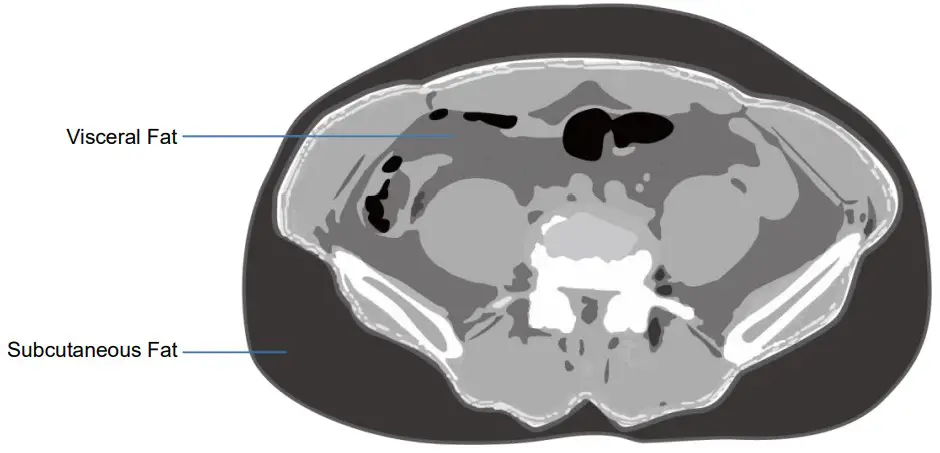

C. Visceral Fat Area

Visceral fat refers to fat accumulated around the intraperitoneal mesentery and the periphery (a broad membrane striking the abdominal wall from the lower part of the stomach). Visceral fat area is the cross sectional area of the fat in between the 4th and 5th lumbar vertebrae. As visceral fat accumulates, insulin is excessively secreted and cardiovascular diseases tends to increase. Thus, it is imperative to be cautious with the accumulation of visceral fat.

Moreover, even if the body fat percentage of the body weight falls within the standard range, one should aim for a healthy diet if there is an excessive visceral fat accumulation (refraining from eating sugar rich food, fatty food, refined grains, etc.) It is also important to participate in cardiovascular exercise in preventing accumulation of excessive visceral fat.

| Visceral Fat Area (0.0 ~ 100.0cm²) | 79.8 |

D. Subcutaneous Fat Area

The subcutaneous fat area is located between the dermis and fascia of the skin and represents fat that serves to store nutrients, block heat, absorb shock, etc. The subcutaneous fat area is measured by measuring the cross section between 4th and 5th lumbar vertebrae to the outside of the peritoneum. The subcutaneous fat has less association with diseases in comparison to the visceral fat but should be watched with caution as excessive accumulation may cause increase in weight, causing musculoskeletal disorders.

| Subcutaneous Fat Area (0.0 ~ 200.0cm²) | 128.7 |

E. Visceral to Subcutaneous Fat Ratio (VSR)

Visceral to Subcutaneous Fat Ratio (VSR) refers to the value of the visceral fat area divided by subcutaneous fat ratio.

Visceral to Subcutaneous Fat Ratio(VSR) = Visceral Fat Area / Subcutaneous fat Ratio

| VSR (0.0 ~ 0.4) | 0.62 |

Even if the fat percentage is identical, the degree of risk to health varies depending on the location of fat distribution. When fat accumulates in the abdomen and abdominal obesity occurs, it is vulnerable to type 2 diabetes, hyperlipidemia, high blood pressure, coronary artery disease. In particular, as the amount of visceral fat accumulates, there is a higher risk of getting the disease mentioned above. Visceral to Subcutaneous Fat Ratio (VSR) is one of the criteria in assessing the accumulation of visceral fat, with individuals with values of over 0.4 considered obese when it comes to intra-abdominal obesity.

Visceral fat is highly influenced by one’s lifestyle and habits, and thus controlled diet and exercise alone can bring a lot of changes. Exercise therapy particularly plays a major role in the reduction of visceral fat, so if one’s VSR is over 0.4, daily cardiovascular exercise of at least an hour is recommended.